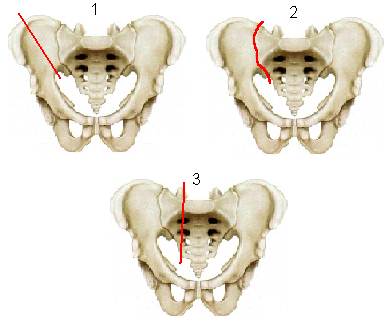

I. Краевые переломы отделов таза, не участвующих в образовании тазового кольца (рис.1):

1. отрыв передне-верхней ости подвздошной кости,

2. отрыв передне-нижней ости подвздошной кости,

3. краевой перелом крыла подвздошной кости.

4. переломы крестца ниже крестцово-подвздошного сочленения и копчика,

5. перелом седалищного бугра.

Рис.1. Краевые переломы отделов таза, не участвующих в образовании тазового кольца.